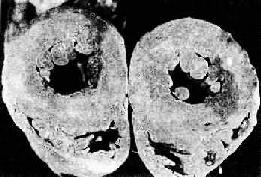

2. 心脏的病变 主要为左心室肥大,这是对持续性血压升高心肌工作负荷增加的一种适应性反应。在心脏处于代偿期时,肥大的心脏心腔不扩张,甚至略微缩小,称为向心性肥大 (concentric hypertrophy)。心脏重量增加,一般达400g以上,甚至可增重1倍。肉眼观,左心室壁增厚,可达1.5~2cm;左心室乳头肌肉柱明显增粗 (图8-11)。镜检下,肥大的心肌细胞变粗,变长,并有较多分支。细胞核较长、较大(可形成多倍体)。由于不断增大的心肌细胞与毛细血管供养之间的不相 适应,加上高血压性血管病,以及并发动脉粥样硬化所致的血供不足,便导致心肌收缩力降低,逐渐出现心腔扩张,称为离心性肥大(eccentric hypertrophy)。严重者可发生心力衰竭。

高血压病时左心室向心性肥大(心脏横断面)

图8-11 高血压病时左心室向心性肥大(心脏横断面)

左心室壁增厚,乳头肌显著增粗